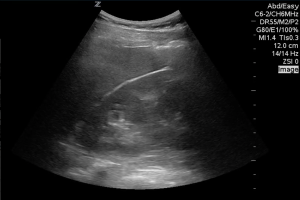

This is a view of a patient’s left upper quadrant, there is a hypoechoic area in the splenorenal interface.

…but is it free fluid?

Unless you have just been taken off the laparoscopy table, there is no open space in the peritoneum, only potential space. Fluid must wedge itself between organs and the parietal/ retro-peritoneum. It doesn’t make sense for it to just disappear or divert from a peritoneal organ, it should follow the contour of the organ and ultimately taper of creating a ‘pointy’ appearance like this:

On further investigation the area in the first image was found to be a large renal cyst, this is a short axis view of the same area…